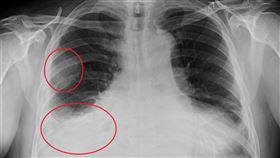

肺部「毛玻璃」影像嚇壞 醫:不等於癌症

隨著低劑量電腦斷層掃描(LDCT)被廣泛納入健檢項目...